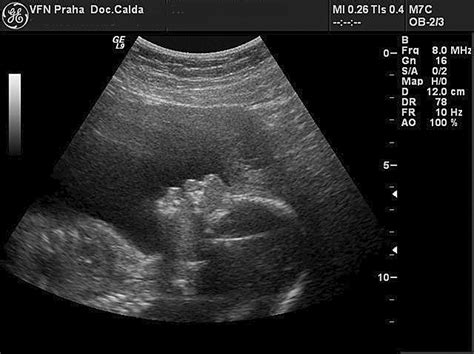

V 28. týždni tehotenstva, ktorý označuje začiatok tretieho trimestra, má vaše bábätko veľkosť zrelého baklažánu, šalátovej hlavy alebo dokonca kokosového orecha. Meria už približne 36-38 cm (od hlavičky po päty) a váži okolo 900 gramov až 1,2 kg. Ak by sa narodilo v tomto týždni, so špecializovanou starostlivosťou má vyše 90% šancu na prežitie. Jeho srdiečko bije rýchlosťou 150 úderov za minútu, čo je možné počuť cez stetoskop.

V tomto období už dieťa nemá v maternici toľko priestoru na kotrmelce ako predtým. Namiesto intenzívnej gymnastiky sa len prevaľuje a opiera jednotlivými časťami telíčka o stenu vášho bruška. Keď si na vydutiny priložíte dlane, môžete nahmatať hlavičku, pästičku, lakeť či nôžku.

Niektoré bábätká sa v týchto týždňoch už otáčajú dolu hlavičkou, pripravené v tejto pozícii na pôrod. Ak sa tak ešte nestalo a dieťa sa stále otáča hlavou hore či priečne, nezúfajte, to sa ešte v nadchádzajúcich týždňoch môže zmeniť.